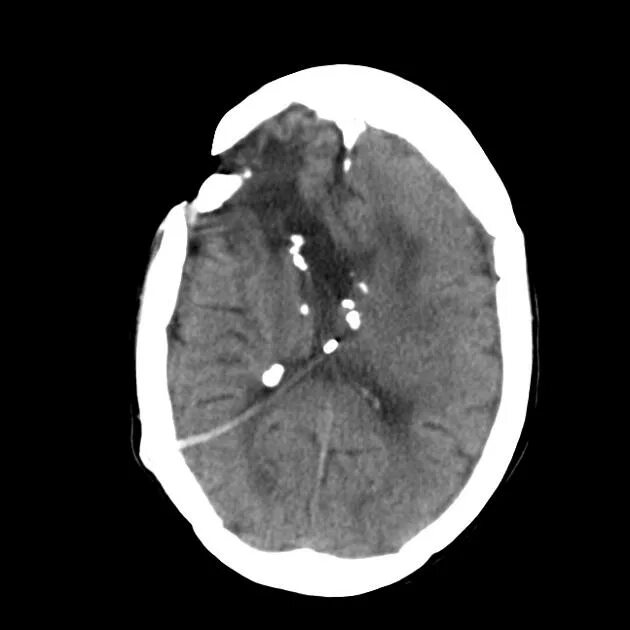

Туберкулезный склероз